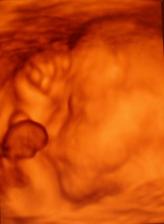

19.3.2010 - 4D utz - Byl to úžasný zážitek. Davídek se sice nejdřív nechtěl ukázat, ale nakonec si dal říct a pootočil se a ukázal nám jeho krásný obličejík 🙂)) je jak panenka s naducanýma tvářičkama 🙂)